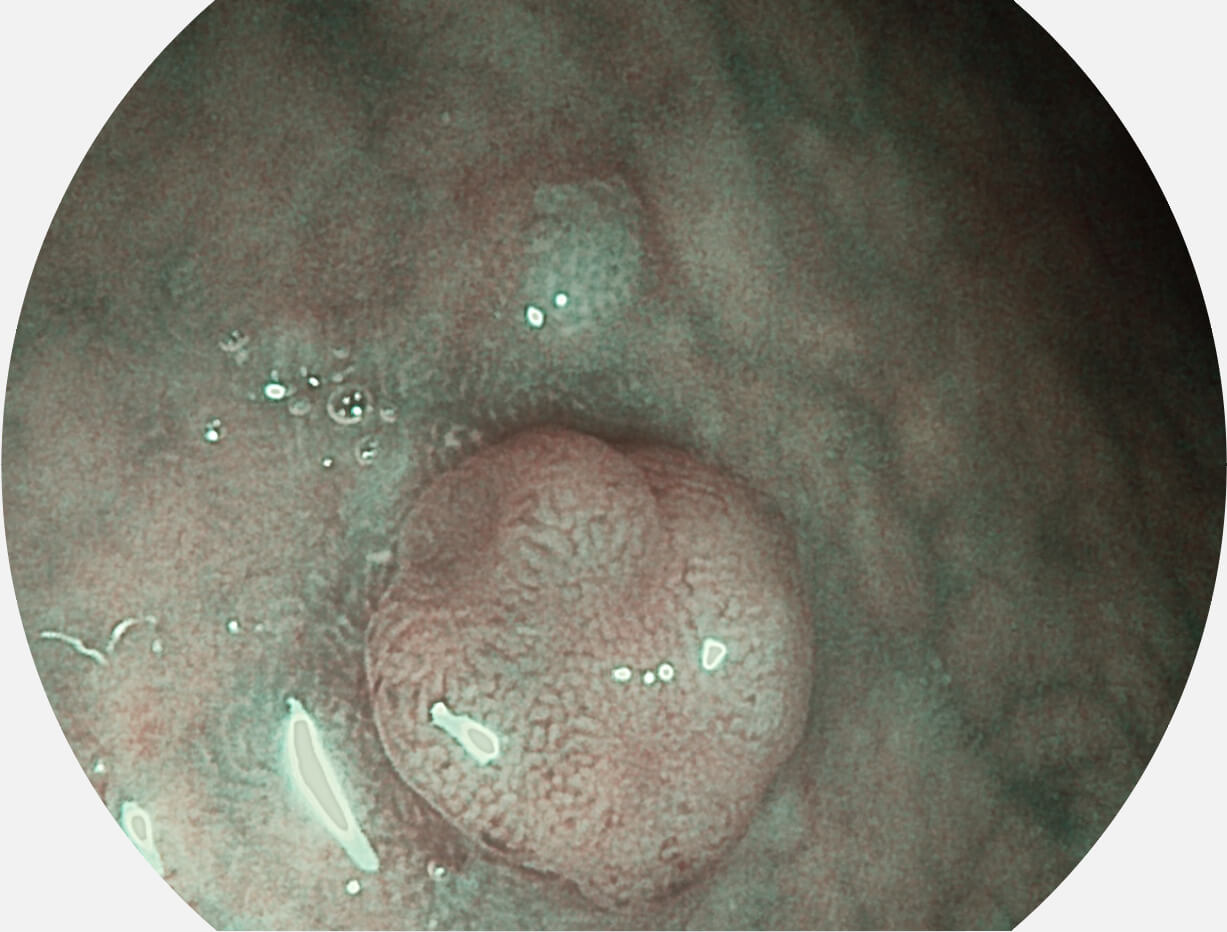

Versatile Intelligent Staining Technology, VIST

强调浅层黏膜结构的同时,保证照明亮度和提升浅层微血管与中层血管颜色对比度,病变边界更清晰。

白光图像

VIST图像